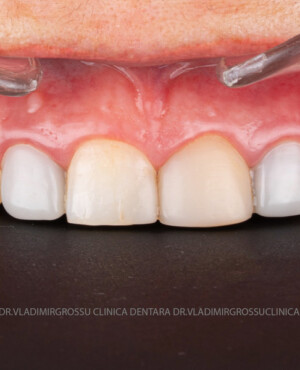

Stabilirea lungimii și formei dinților pentru efectul de întinerire

Parametrii estetici ai dinților – lungime, lățime și formă – se adaptează caracteristicilor anatomice individuale ale pacientului. Orizontul zâmbetului corespunde, în general, orizontului pupilelor, iar lungimea dinților este influențată de scheletul maxilarului superior, poziția și mobilitatea buzei superioare. Totuși, frumusețea este subiectivă și personalizată.

Transformările estetice și impactul reabilitării asupra vieții pacienților

Reabilitarea dentară produce o schimbare vizibilă și profundă în aspectul pacientului, cu efecte pozitive evidente asupra stimei de sine și a calității vieții. Mulți pacienți relatează bucuria redobândirii funcției masticatorii și dispariția complexelor legate de aspectul dentar.